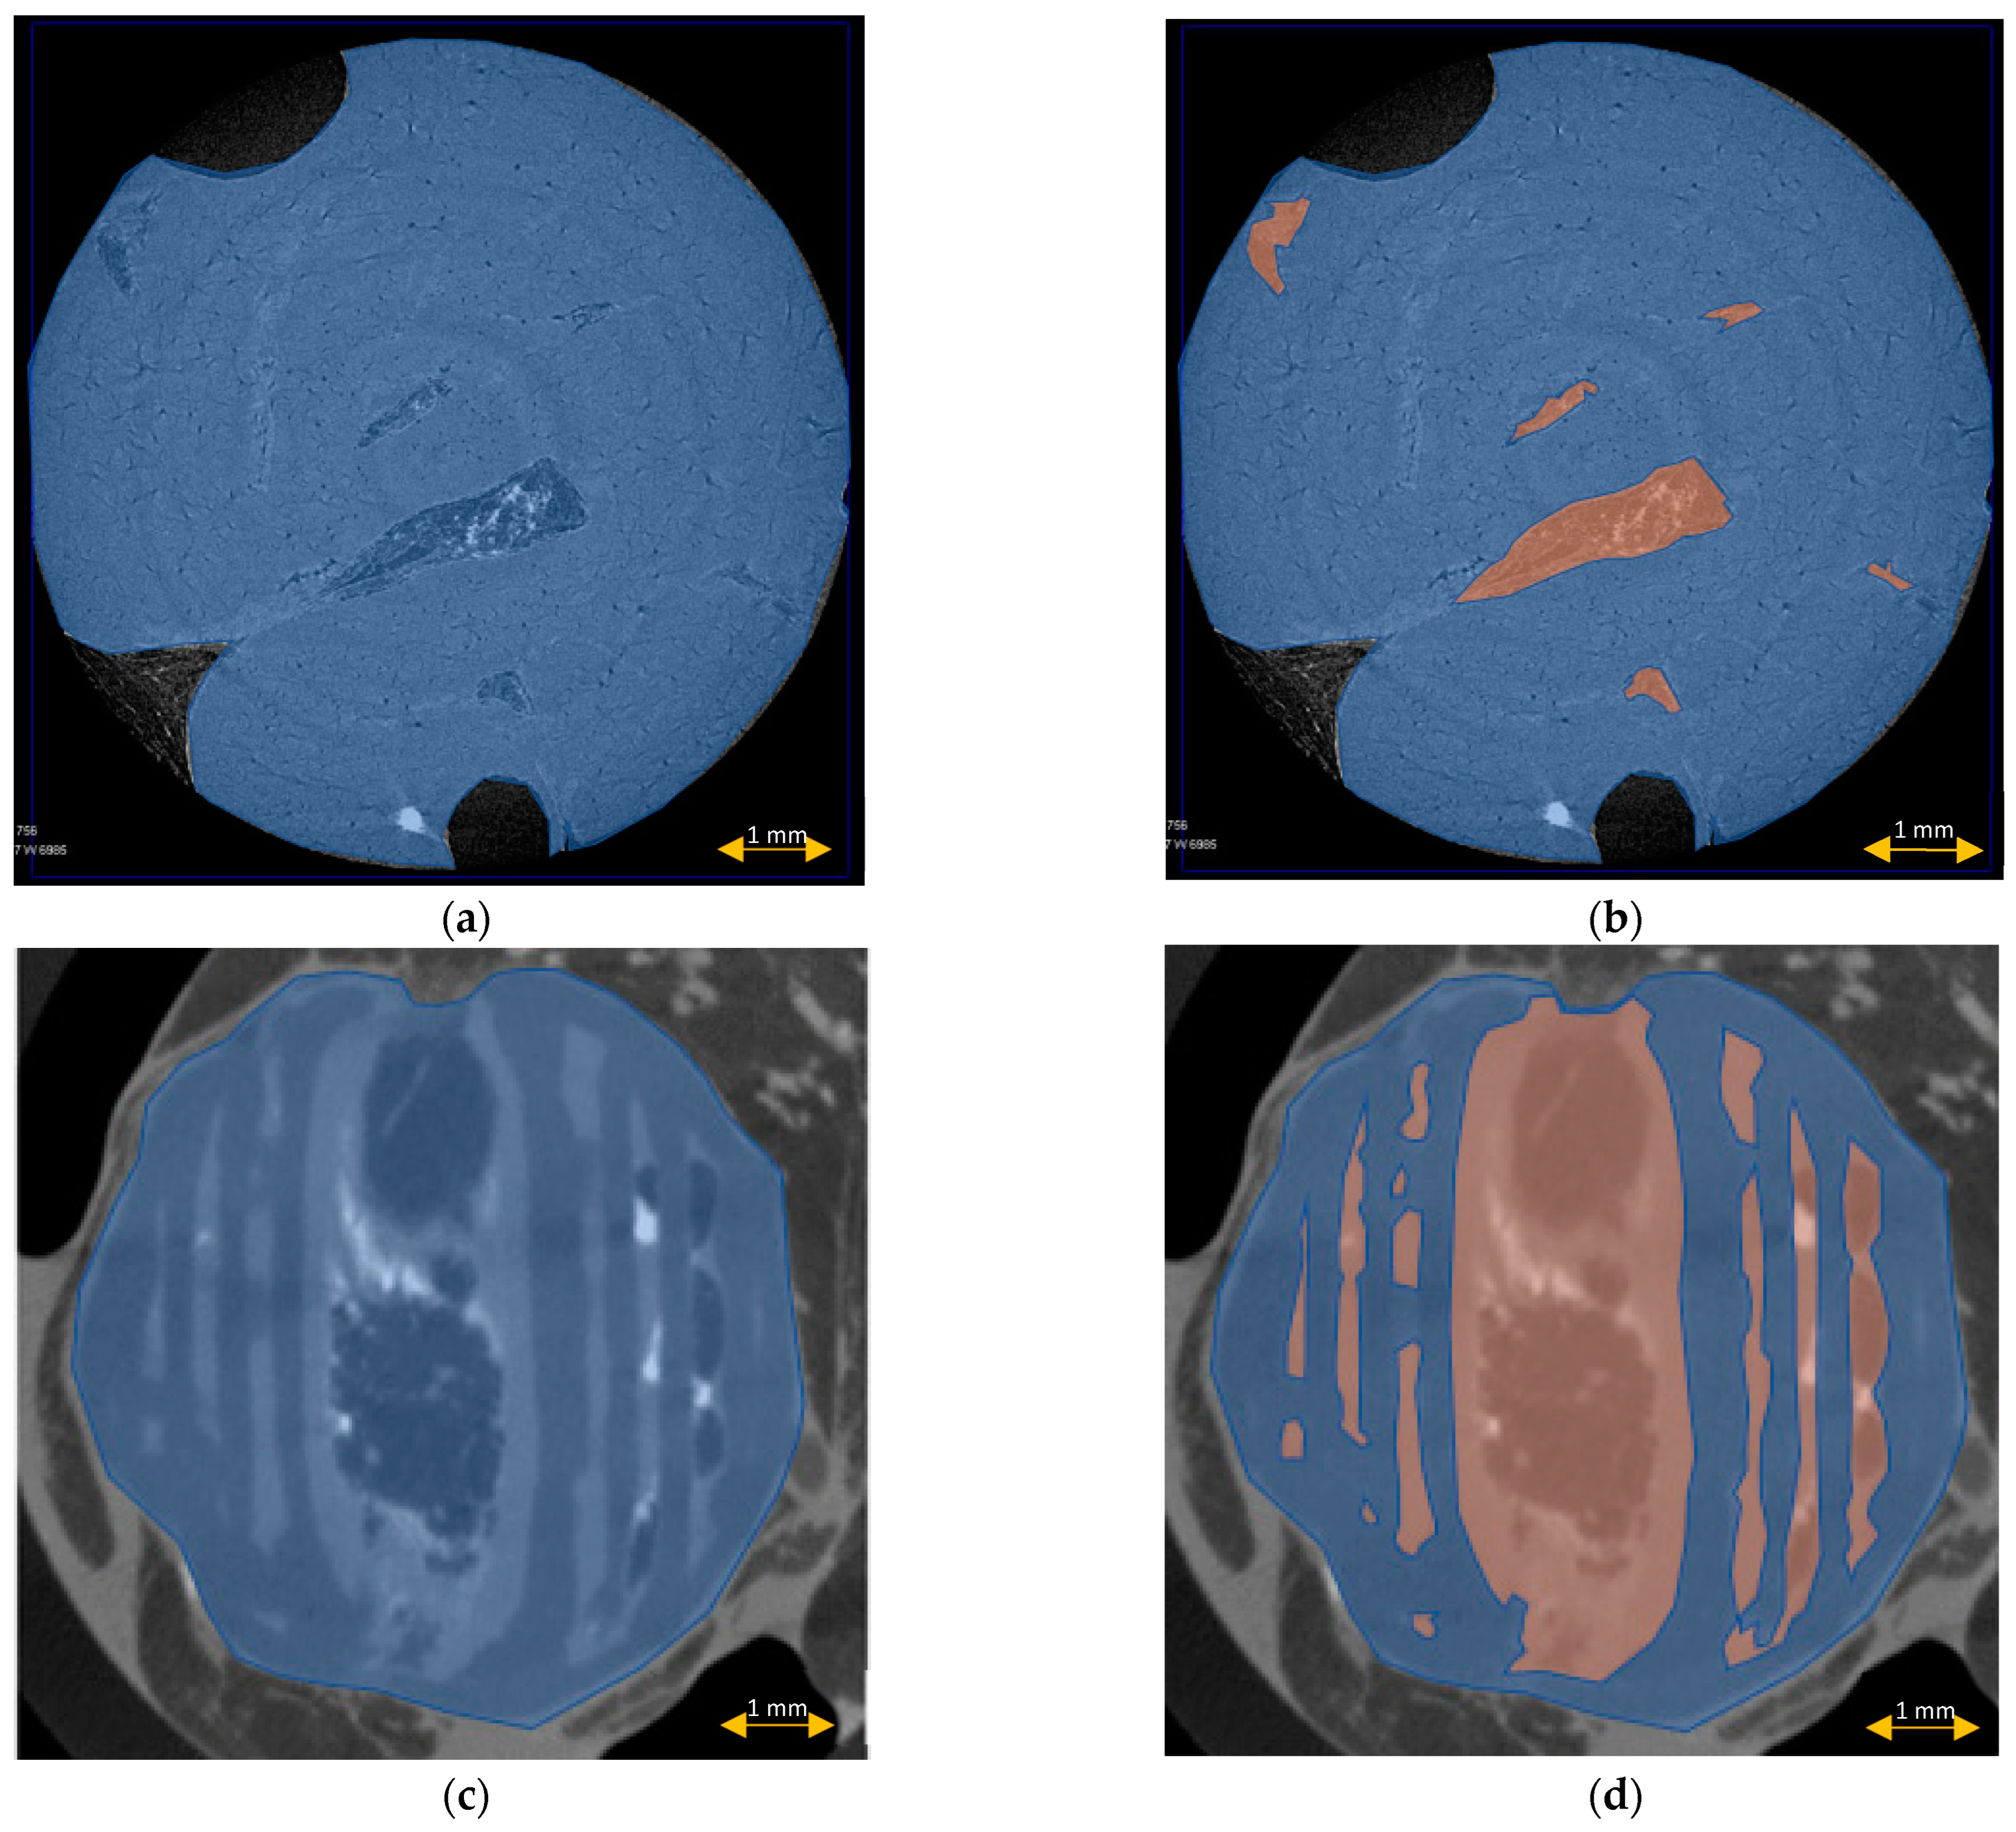

3.5. Scaffold μCT Imaging

3.6. Scaffold Cross-Sectional Analysis